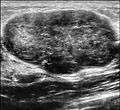

Fibroadenoma in ultrasound